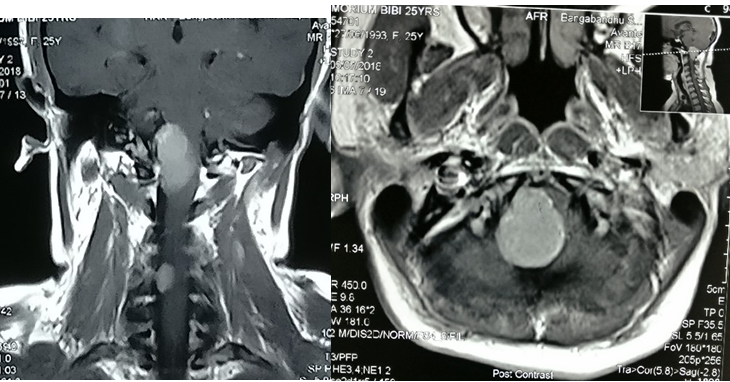

A 34years male admitted in our Department of Neurosurgery with the complaints of neck pain for 2year, progressive weakness of all limbs in the form of rotating paralysis starting with left upper limb followed by left lower limb, right lower limb & right upper limb for 15months without bowel bladder disturbance. On neurological examinations patients was found to be quadriparetic having muscle power MRC grade 3 on both side rendering her gait to be hemiplegic and walk with support. All her deep tendon reflexes were exaggerated. Hoffman sign was positive bilaterally.  Planters were bilaterally extensor. Ankle clonus was present bilaterally. He did not have any hypo or hyper pigmented patch in any part of the body. MRI of brain & cervical spine showed an intra-dural extra medullary lesion measuring about 5 x 3.5cm at foramen magnum extending both up and down situated posteriorly more on left side (Figures 4A-C). There was no other lesion on further cranial & spinal screening MRI.

Figure 4MRI of brain & cervical spine showed an intra-dural extra medullary lesion measuring about 5 x 3.5 cm at foramen magnum extending both up and down situated posteriorly more on left side.